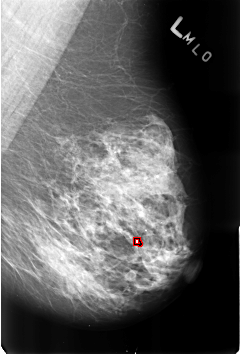

B_3174_1.LEFT_MLO

LEFT_MLO LINES 4592 PIXELS_PER_LINE 3120 BITS_PER_PIXEL 12 RESOLUTION 50 OVERLAY

FILE: B_3174_1.LEFT_MLO.OVERLAY

TOTAL_ABNORMALITIES 1

ABNORMALITY 1

LESION_TYPE CALCIFICATION TYPE ROUND_AND_REGULAR-LUCENT_CENTER-DYSTROPHIC DISTRIBUTION DIFFUSELY_SCATTERED

ASSESSMENT 2

SUBTLETY 4

PATHOLOGY BENIGN_WITHOUT_CALLBACK

TOTAL_OUTLINES 1

BOUNDARY